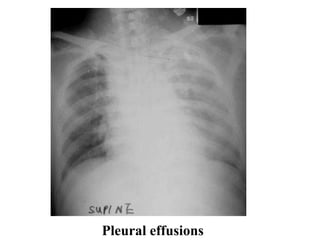

Pleural effusions